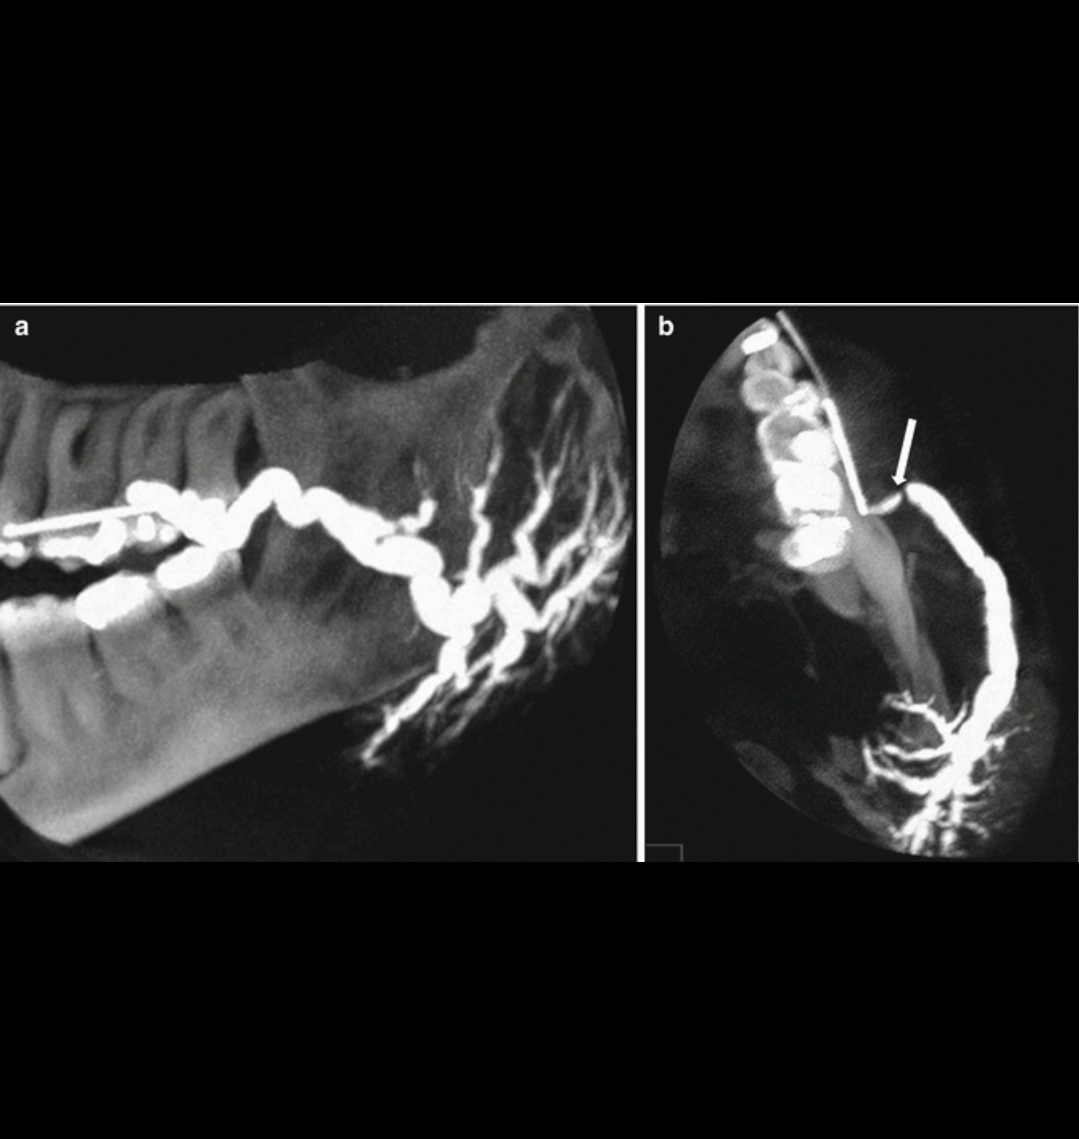

Sialography<br />INDICATIONS <br />1. Calculi.<br />2. Chronic inflammatory disease.<br />3. Mass lesion.<br />4. Obstructive lesion.<br />5. Penetrating trauma.<br />6. Strictures.<br />7. Fistula.<br />8. Prior to CT evaluation of salivary glands.<br /><br />CONTRAINDICATIONS <br />1. Allergy to iodine.<br />2. Acute Sialadenitis.<br /><br />EQUIPMENT <br />1. Contrast medium-water soluble, ionic contrast media like<br />Triovideo 280,Conray 280 or non-ionic contrast medium such as<br />omnipaque-350.<br />2. Lacrimal cannula or disposable 22 G (Gelco/Venflon).<br />3. Lacrimal dilator. Liebreich's double ended lacrimal probe.<br />4. 2 cc syringe. Four grades (00/0, 1/2, 3/4 & 5/6) 00/0 and ½<br />are required for sialography. Outer diametre of cannula 1.02 mm.<br />Rabinov sialography catheter obtainable in a sterile pack and is<br />recommonded.<br />5. Lemon/vitamin C tablet.<br /><br />PROCEDURE <br />l. Preliminary radiograph<br />Plain radiograph should be taken before embarking on sialography<br />because a considerable pathology is associated with opaque calculi<br />within the glands themselves or their ducts, particularly in the<br />submandibular gland.<br />2. Locating duct openings<br />(a) Parotid duct opens opposite 2nd upper molar tooth on the<br />buccal surface of the cheek.<br />(b) Submandibular duct opens at the base of the frenulum of the<br />tongue.<br />(c) In case the ostium is not visible, apply pressure on the gland<br />or give a sialogogue like lime. Then saliva will be seen pouring<br />through the punctum.<br />3. Dilate the punctum with lacrimal dilator.<br />4. Technique<br />Two techniques for cannulating the ducts are by using:<br />(a) Intracath technique.<br />(b) Lacrimal cannula technique.<br />• If we are using an intracath, we should cut enough plastic<br />tubing from the tip of intracath with fine scissors such that<br />2 mm of the inner wire stilette is still protruding. Now the<br />punctum is cannulated for 5 mm. Now withdraw the stilette<br />such that it no longer protrudes the outer tube.<br />• The inner stilette produces stiffness during introduction of<br />catheter. The stilette is removed and outer tube is attached to<br />polythene tube.<br />• Now the contrast is injected.<br />• In the lacrimal cannula method, contrast is injected into the<br />cannula which is introduced through the duct opening<br />• Contrast is injected till the patient complains of pain by a<br />prearranged signal.<br />• About 0.5-1.0 cc of contrast is required.<br />5. Film exposure<br />Positioning for parotids:<br />• Frontal view is taken with face rotated 5-10 degrees towards<br />the side of study.<br />• Lateral view is taken with 15-20 degrees cranial tube tilt.<br />Positioning for submandibular gland<br />• Lateral view is taken with 15-20 degrees cranial tube tilt.<br />Films are taken during injection. The catheter is left in place<br />till the adequacy of films is ensured.<br />6. Aftercare: none<br />If sialadenitis occurs after the procedure, it should be treated with<br />antibiotics and anti-inflammatory drugs.<br />7. Complications<br />• Sialadenitis and abscess<br />• Stricture of the ducts.<br />8. Disadvantages of sialogram<br />• Masses less than 1cm may not be detected.<br />• Contrast does not always penetrate the deep lobe of parotid<br />gland.<br />